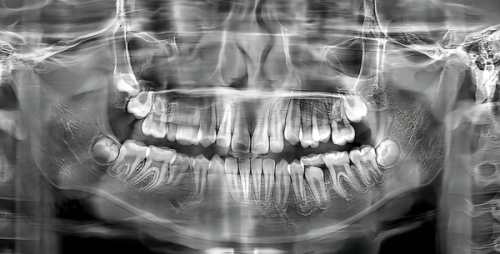

近年来,医院在口腔数字化临床应用等重点领域实现关键技术突破,开展的新技术如基于数字化导板的复杂阻生牙、多生牙拔除、牙颌面畸形综合矫治技术、儿童舒适化口腔治疗等,有效填补省内乃至国内外空白。就拿基于数字化导板的复杂阻生牙、多生牙拔除来说,以前拔除这些牙齿可能就像在黑暗中摸索,而现在有了数字化导板,就像是有了一个精细的地图,医生可以更加正确地进行操作,大大提高了手术的成功几率和安心性。